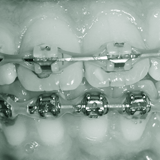

Behandlung PARODONTOLOGIE ENDODONTIE CHIRURGIE IMPLANTOLOGIE PROTHETIK ÄSTHETISCHE ZHK KIEFERORTHOPÄDIE KINDERZAHNHEILK.